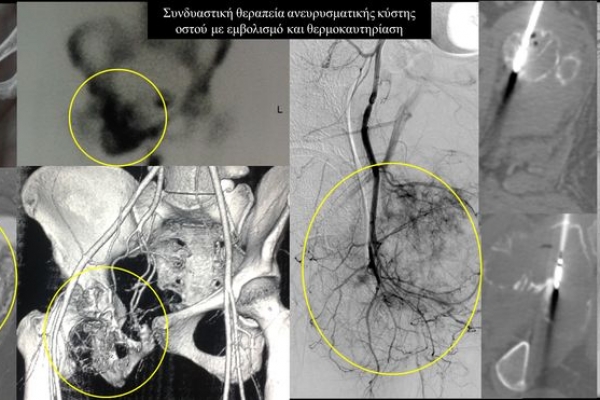

Η αντιμετώπιση του καρκινικού πόνου, εκτός από την κλασική συντηρητική φαρμακευτική θεραπεία, όταν ο πόνος επιμένει ή όταν οι παρενέργειες των φαρμακευτικών μεθόδων εξαντλούν τον ασθενή, περιλαμβάνει ελάχιστα παρεμβατικές τεχνικές με τις οποίες επιτυγχάνεται διακοπή ή καταστροφή της νευρικής οδού μεταβίβασης του πόνου. Η επεμβατική ακτινολογία διαθέτει μια πληθώρα θεραπευτικών τεχνικών που σκοπό έχουν να προσφέρουν ποιοτική βελτίωση της ζωής και των σχέσεων, τόσο των ογκολογικών ασθενών, όσο και των οικογενειών τους.